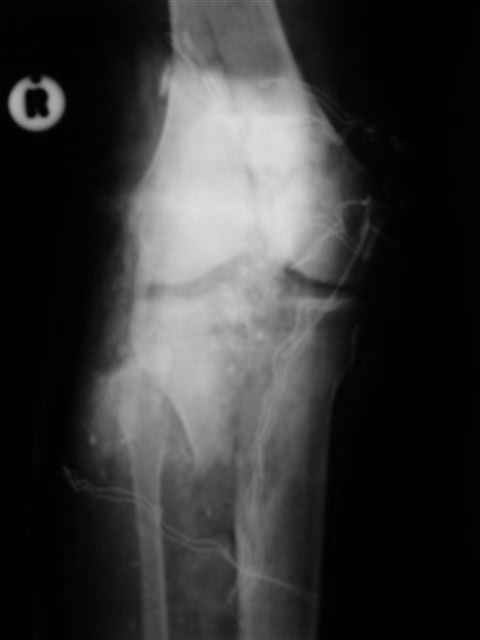

А можно,пожалуйста, более конкретно про повреждение голеностопного сустава?

В первом письме я упомянул о закрытом повреждении правого голеностопного сустава, эверсионно-пронационный механизм травмы - перелом внутренней лодыжки( поперечный, на уровне суставной щели) и отрывной перелом бугорка Chaput. После обработки открытых переломов бедра и большеберцовой кости в эту же сессию перелом внутренней лодыжки фиксировал двумя расходящимися спицами, бугорок Chaput двумя тягловыми винтами 3,5 мм. Раны заживают благополучно. Учитывая повреждение наружной группы мышц, активное разгибание в голеностопном суставе ограничено. Пассивная + пассивно-активная мобилизация голеностопного сустава с физиотерапевтом.

Каких-либо вопросов по лечению травмы голеностопного сустава у меня не возникло,поэтому о дальнейших деталях лечения я не упоминал.

(Если вы заинтересовались, то Рг граммы представлю)

Уважаемый Иван,

Я предупреждал, что ничего сверхъестественного. Каюсь, что одна из спиц прошла несколько дальше, чем нужно было, но главное - перелом стабилизирован и больной работает суставом в полном объёме, несмотря на представленную раннее травму коленного сустава.